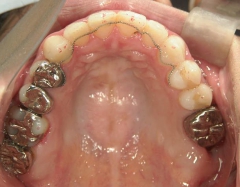

矯正歯科 治療前 上顎を装置(QH)で拡大後ワイヤー矯正へ移行、右下5番左下4番 計2本抜歯叢生改善

矯正_灰色.pngno.28_6958_治療後_上.jpg矯正_灰色.png

矯正_灰色.pngno.28_6958_治療後_下.jpg矯正_灰色.png